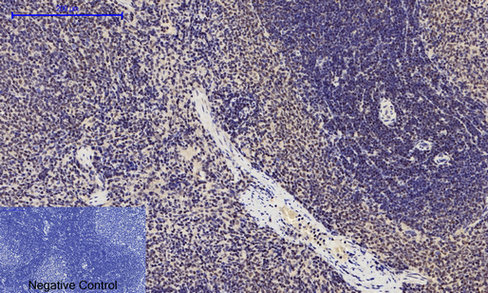

- Immunohistochemistry analysis of paraffin-embedded rat spleen tissue using Phospho-p53 (Ser15) antibody.High-pressure and temperature Sodium Citrate pH 6.0 was used for antigen retrieval.